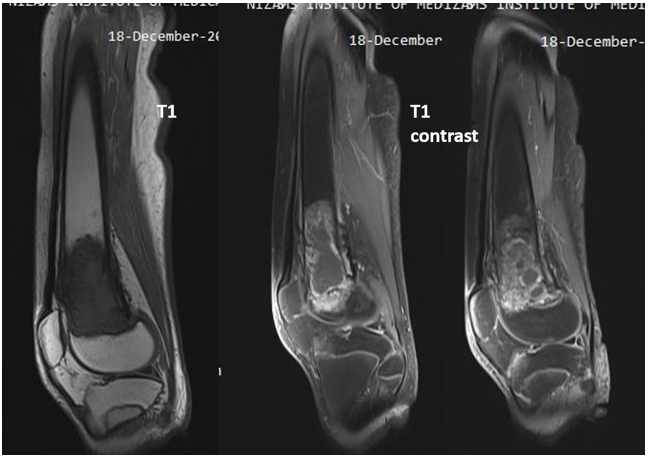

Figure 5: 14 year-old male; OS distal femur, transphyseal extension and no soft tissue involvement in contrast enhanced T1w sagittal images.